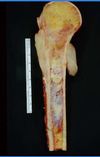

What is this lesion?

Chondrosarcoma The gross image shows a destructive cartilaginous lesion